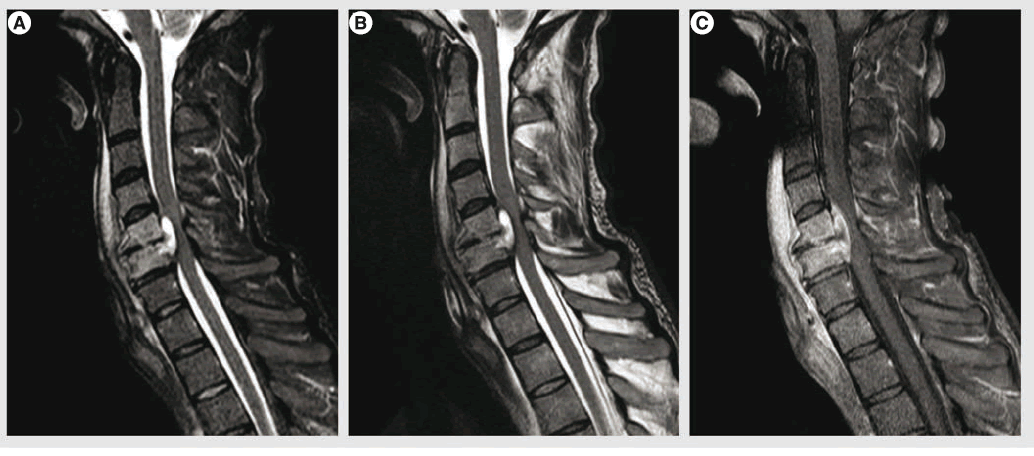

Trên thế giới, áp xe ngoài màng tủy thuộc loại hiếm. Tuy nhiên ở Việt Nam, bệnh lý này khá phổ biến do tình hình bệnh lao đang có xu hướng tăng. Nguyên nhân gây bệnh là do các ổ nhiễm trùng ở xa hoặc các ổ nhiễm trùng gần kề như lao cột sống, nhiễm trùng sau các can thiệp vùng cột, áp xe cũng có thể do ổ nhiễm trùng từ nơi khác tới như sau nhiễm trùng,...

Tùy vị trí và mức độ chèn ép của khối áp xe mà biểu hiện liệt có thể ở hai chi dưới hoặc ở cả hai tay và chân với các mức độ từ nhẹ đến nặng như giảm cảm giác, giảm vận động cho đến mất vận động và mất cảm giác hoàn toàn.

Bên cạnh đó, người bệnh có thể bị rối loạn đại tiểu tiện, thậm chí rối loạn hô hấp và có thể dẫn đến tử vong. Nguyên nhân bệnh nhân bị liệt là do khối áp xe chèn ép trực tiếp vào tủy hay còn gọi là áp xe tủy não hoặc do nhiễm trùng gây ra tắc mạch làm thiếu máu vùng tủy, gây tổn thương tủy.